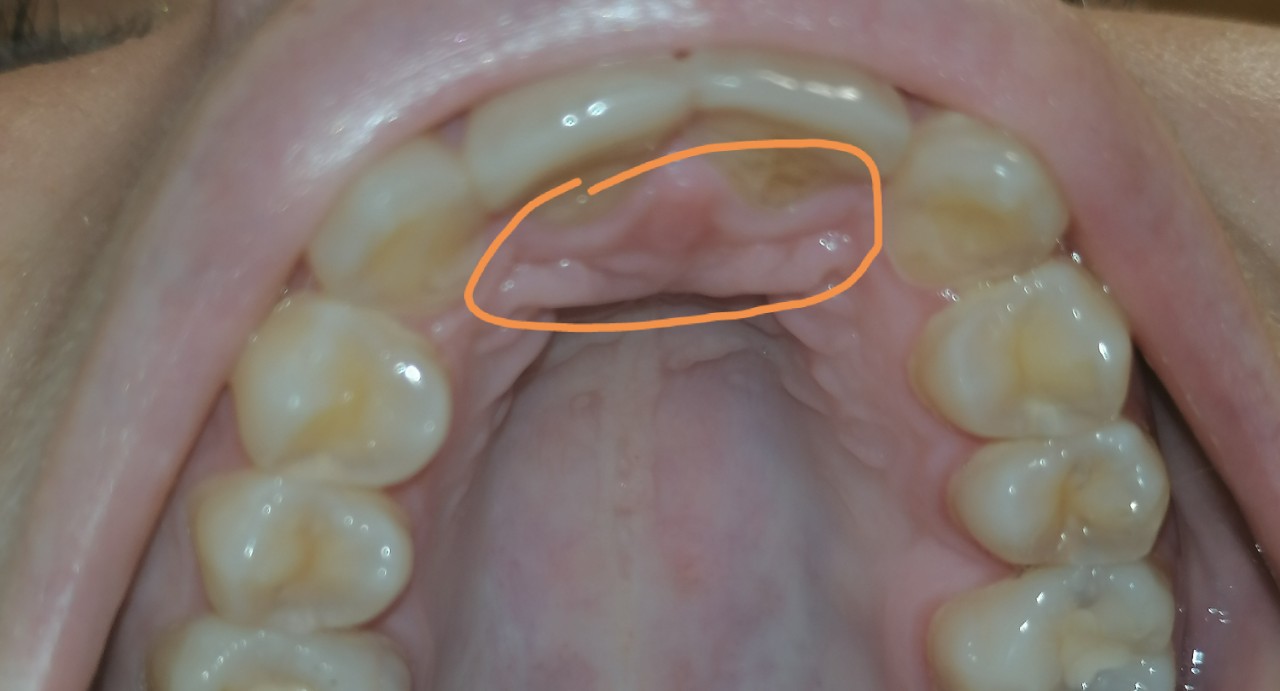

Здравствуйте,13 февраля этого года была проведена реставрация 2-х центральных верхних зубов. Была проблема с эмалью, пошла на реставрацию. Нанесли материал только на внешнюю стенку зуба, сзади на зуб материал не наносился. Начались проблемы через недели 2 после ретставрации. Сзади зубов маленько появился отек(на твердом небе прямо за передними зубами). Беспокоит, что нижние зубы теперь упираются в небо из за то, что там припухло чуть чуть. Уже 11 дней полощу ромашкой и стоматофитом, плюс гель дентамет на 30 минут 2 раза в день наношу. Но не проходит, то отпустит, то опять все по новой. Отек не усиливается. От чего это может быть? И что делать в таком случае, подскажите пожалуйста. Укол в десну ставили по 2 раза над каждым зубом, я просто не понимаю, на что такая реакция. Зубной нитью пользуюсь тоже уже 2 недели.